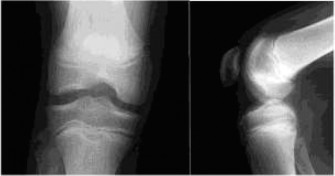

CASE 9 A 14-year-old boy is brought to the ER with complaints of right knee pa…